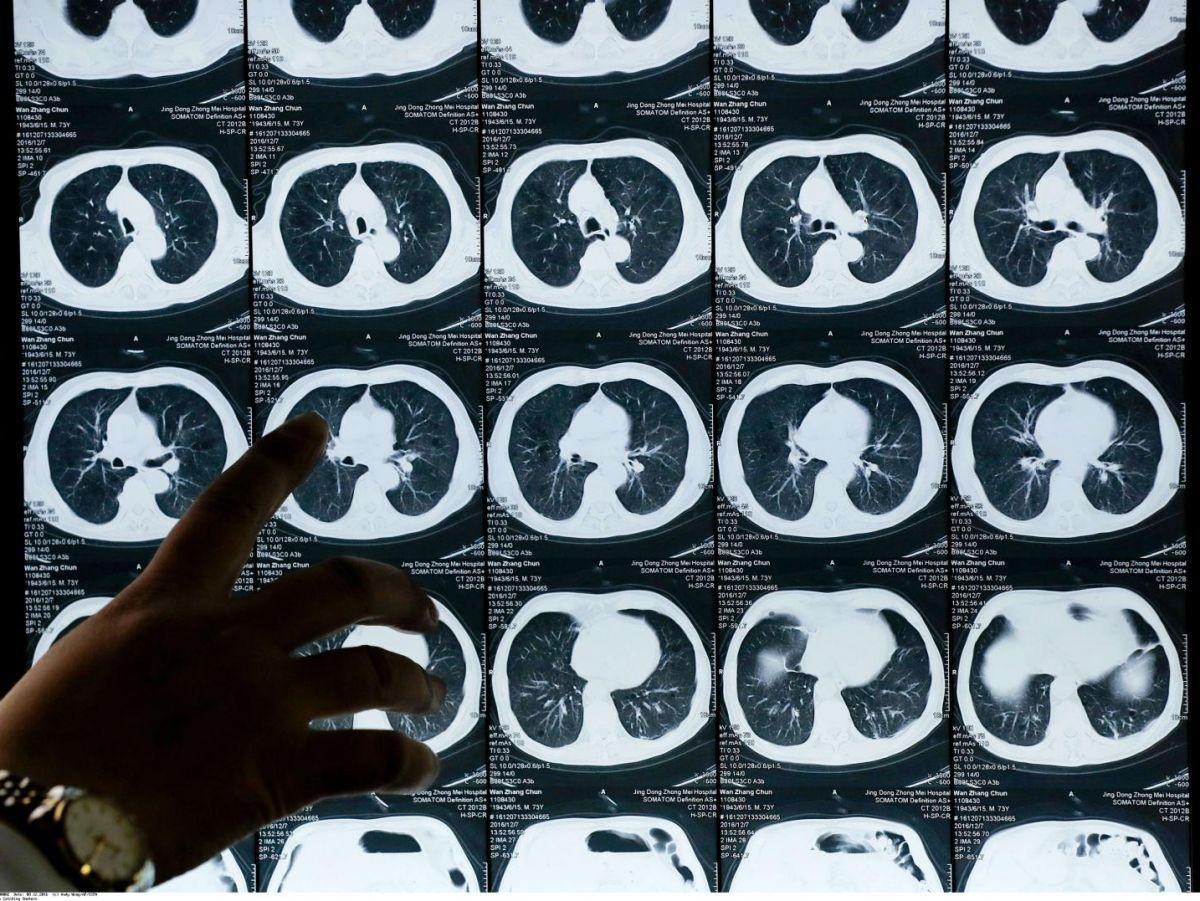

Cette annonce orale a été de plus accompagnée par une publication simultanée dans le New England Journal of Medicine, ce qui vient évidemment renforcer l’importance de son résultat. Elle concerne les patients atteints d’un cancer dit « non à petites cellules », la forme la plus commune de ce type de cancer, présentant un type particulier de mutation, dit de type Egfr, soit environ 10 % à 25 % des patients aux États-Unis et en Europe, 30 % à 40 % en Asie.

Une fois opérés car repérés à un stade précoce, les patients inclus dans l’essai Adaura (environ 700 malades répartis dans une vingtaine de pays) ont été divisés en deux groupes.